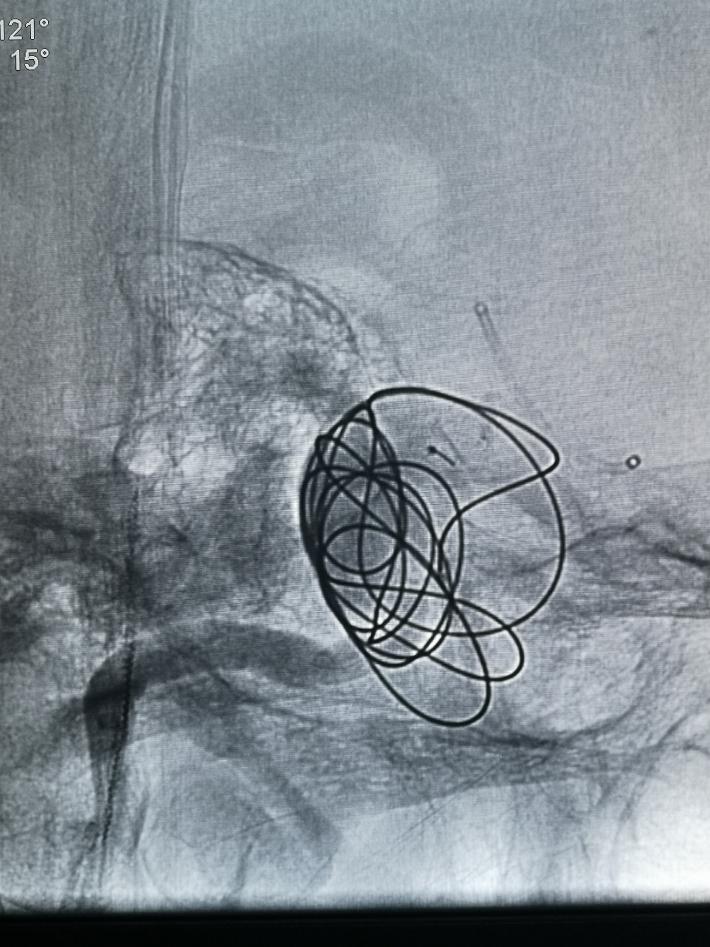

术中我们在密网支架导管无法到位的情况下,选择了常规的“支架辅助下动脉瘤介入栓塞术”,动脉瘤顺利得以治疗,由于瘤体巨大,且患者经济原因,无法做到致密填塞。

术后正侧位造影见,瘤体基本不显影,远端血流流速基本无延迟。